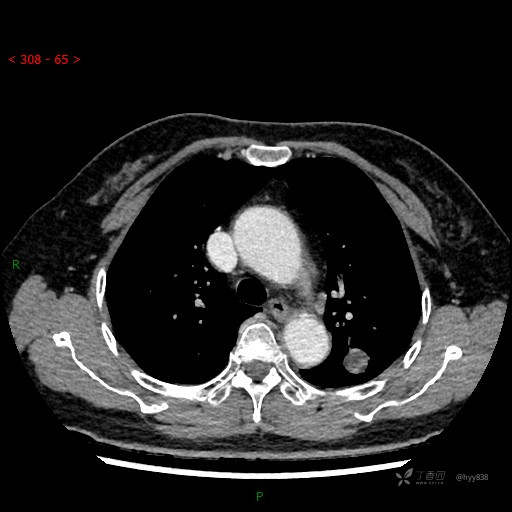

静脉期

各期CT值:28hu、58hu、69hu